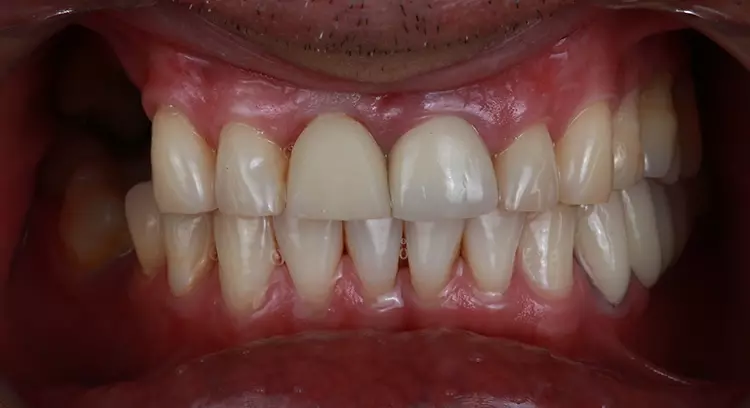

Ein 50-jähriger Patient stellte sich in unserer Zahnklinik vor. Er war mit dem Aussehen seiner Frontzahnkronen unzufrieden. Darüber hinaus klagte er über Schmerzen insbesondere an Zahn 21.

Er berichtete von einem vor 10 Jahren erlittenen Trauma an den oberen mittleren Schneidezähnen. Da die Zähne außerdem kariöse Läsionen aufwiesen, wurden sie endodontisch behandelt und prothetisch mit Zahnkronen versorgt. Der Patient hatte hohe Erwartungen an die bevorstehende Behandlung und erhoffte sich eine deutliche Verbesserung hinsichtlich der Ästhetik und Funktion.

Das Trauma an den oberen mittleren Schneidezähnen führte zu Wurzelresorptionen und einem Mobilitätsgrad 3. Der Patient zeigte Schmerzen an bei der Perkussion von Zahn 21. Die Kronenversorgung der beiden mittleren Schneidezähne war insuffizient.

In beiden Kiefern wurde eine erhebliche Abnutzung der Eckzähne und der Kauflächen im Seitenzahnbereich festgestellt, die zu einem Verlust der anterioren Führung und der vertikalen Dimension führte. Die Zähne 14 bis 17 fehlten.

Das Ergebnis entsprach den Erwartungen des Patienten. In der Nachbehandlungsphase wurde die Okklusion erfolgreich wiederhergestellt, wobei eine neue vertikale Dimension, eine passende Kronenform und -größe sowie funktionsorientierte Okklusionsebenen erreicht wurden.

Es konnten sofortige positive ästhetische und funktionelle Verbesserungen beobachtet werden, die auch 6 Monate nach Eingliederung noch deutlich sichtbar sind. Darüber hinaus wurden okklusale Stabilität und korrekte Zahnführungen erreicht.